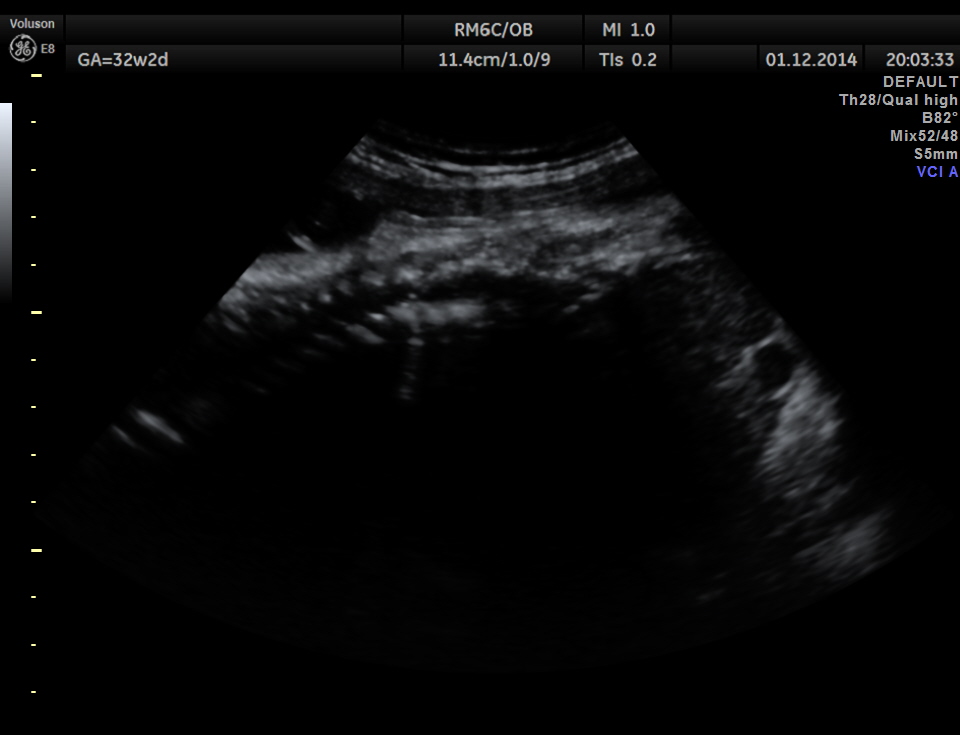

This was a 30 year old lady , with history of consanguinity ; 2nd gravida , 1st child normal ; she has never gone for an ultrasound examination in this pregnancy and was sent by her consultant to a different centre for evaluation . She was found to have hydrocephalus and was referred to our clinic for 2nd opinion.

The following images were obtained.

Hydrocephalus is seen ; Cisterna magna appeared somewhat compressed.

From the ultrasound point of view , we should always look carefully at the spine , in all the cases of hydrocephalus.